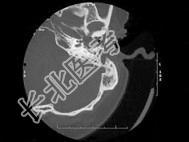

- 单项选择题患者,李某, 20岁,自幼右耳听力较差, 其乳突CT摄片如图所示,可考虑为 ( )

A、先天性外耳道狭窄

B、听神经瘤

C、急性中耳炎

D、先天性胆脂瘤并侵犯耳蜗

E、以上都不是